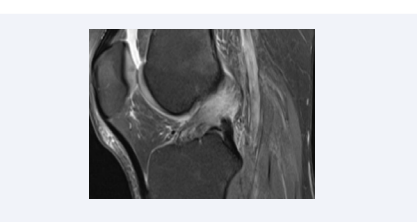

The diagnosis of partial tears of the ACL may be more challenging than complete tears; the sensitivity and specificity of MRI in diagnosing partial tears have been reported to be 40- 75% and 62-89%, respectively [75]. The partially torn ACL shows sagging of the ligament contour with some continuous fibers, and hyperintensity on fluid-sensitive sequences (Figure 5).

Partial tear of the ACL. Sagittal fat-suppressed proton density-weighted image shows partial discontinuity of the ligament fibers with hyperintensity.

Figure 5: Partial tear of the ACL. Sagittal fat-suppressed proton density-weighted image shows partial discontinuity of the ligament fibers with hyperintensity.

The loss of continuity in more than 50% of the ACL fibers indicates a high-grade partial tear, whereas less than 50% of fibers torn is a low-grade partial tear. Partial tears of the ACL may be difficult to differentiate from complete ACL tears, mucoid degeneration of the ACL or even a normal ACL, due to the overlapping imaging features [76].